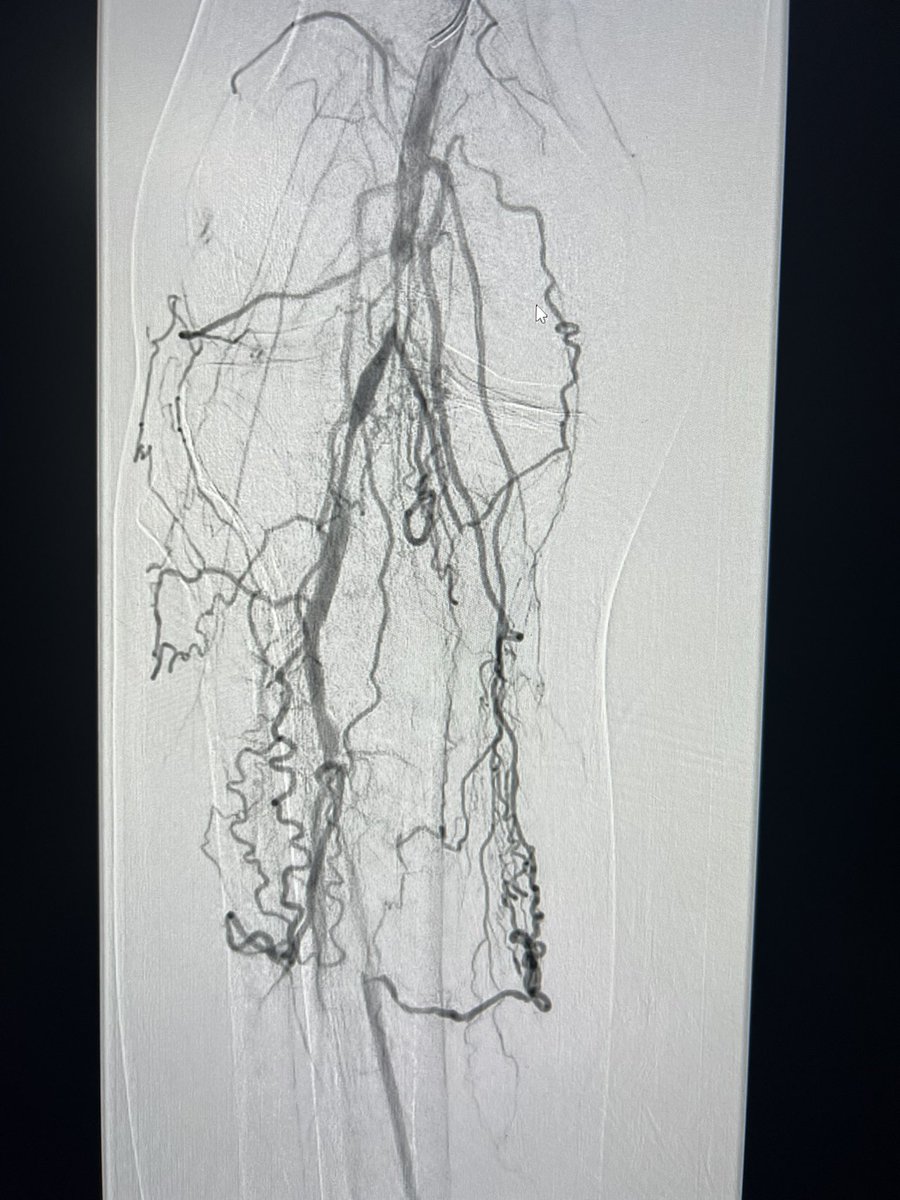

#CLI with Flush #SFA chronic total occlusion , occluded ATA and PTA , distal SFA puncture and #revascularization #amputation prevention #endovascular #IR #interventional #MedTwitter #CTO

banderaldhafery's tweet image. #CLI with Flush #SFA chronic total occlusion , occluded ATA and PTA , distal SFA  puncture and #revascularization #amputation prevention

#endovascular #IR #interventional #MedTwitter #CTO